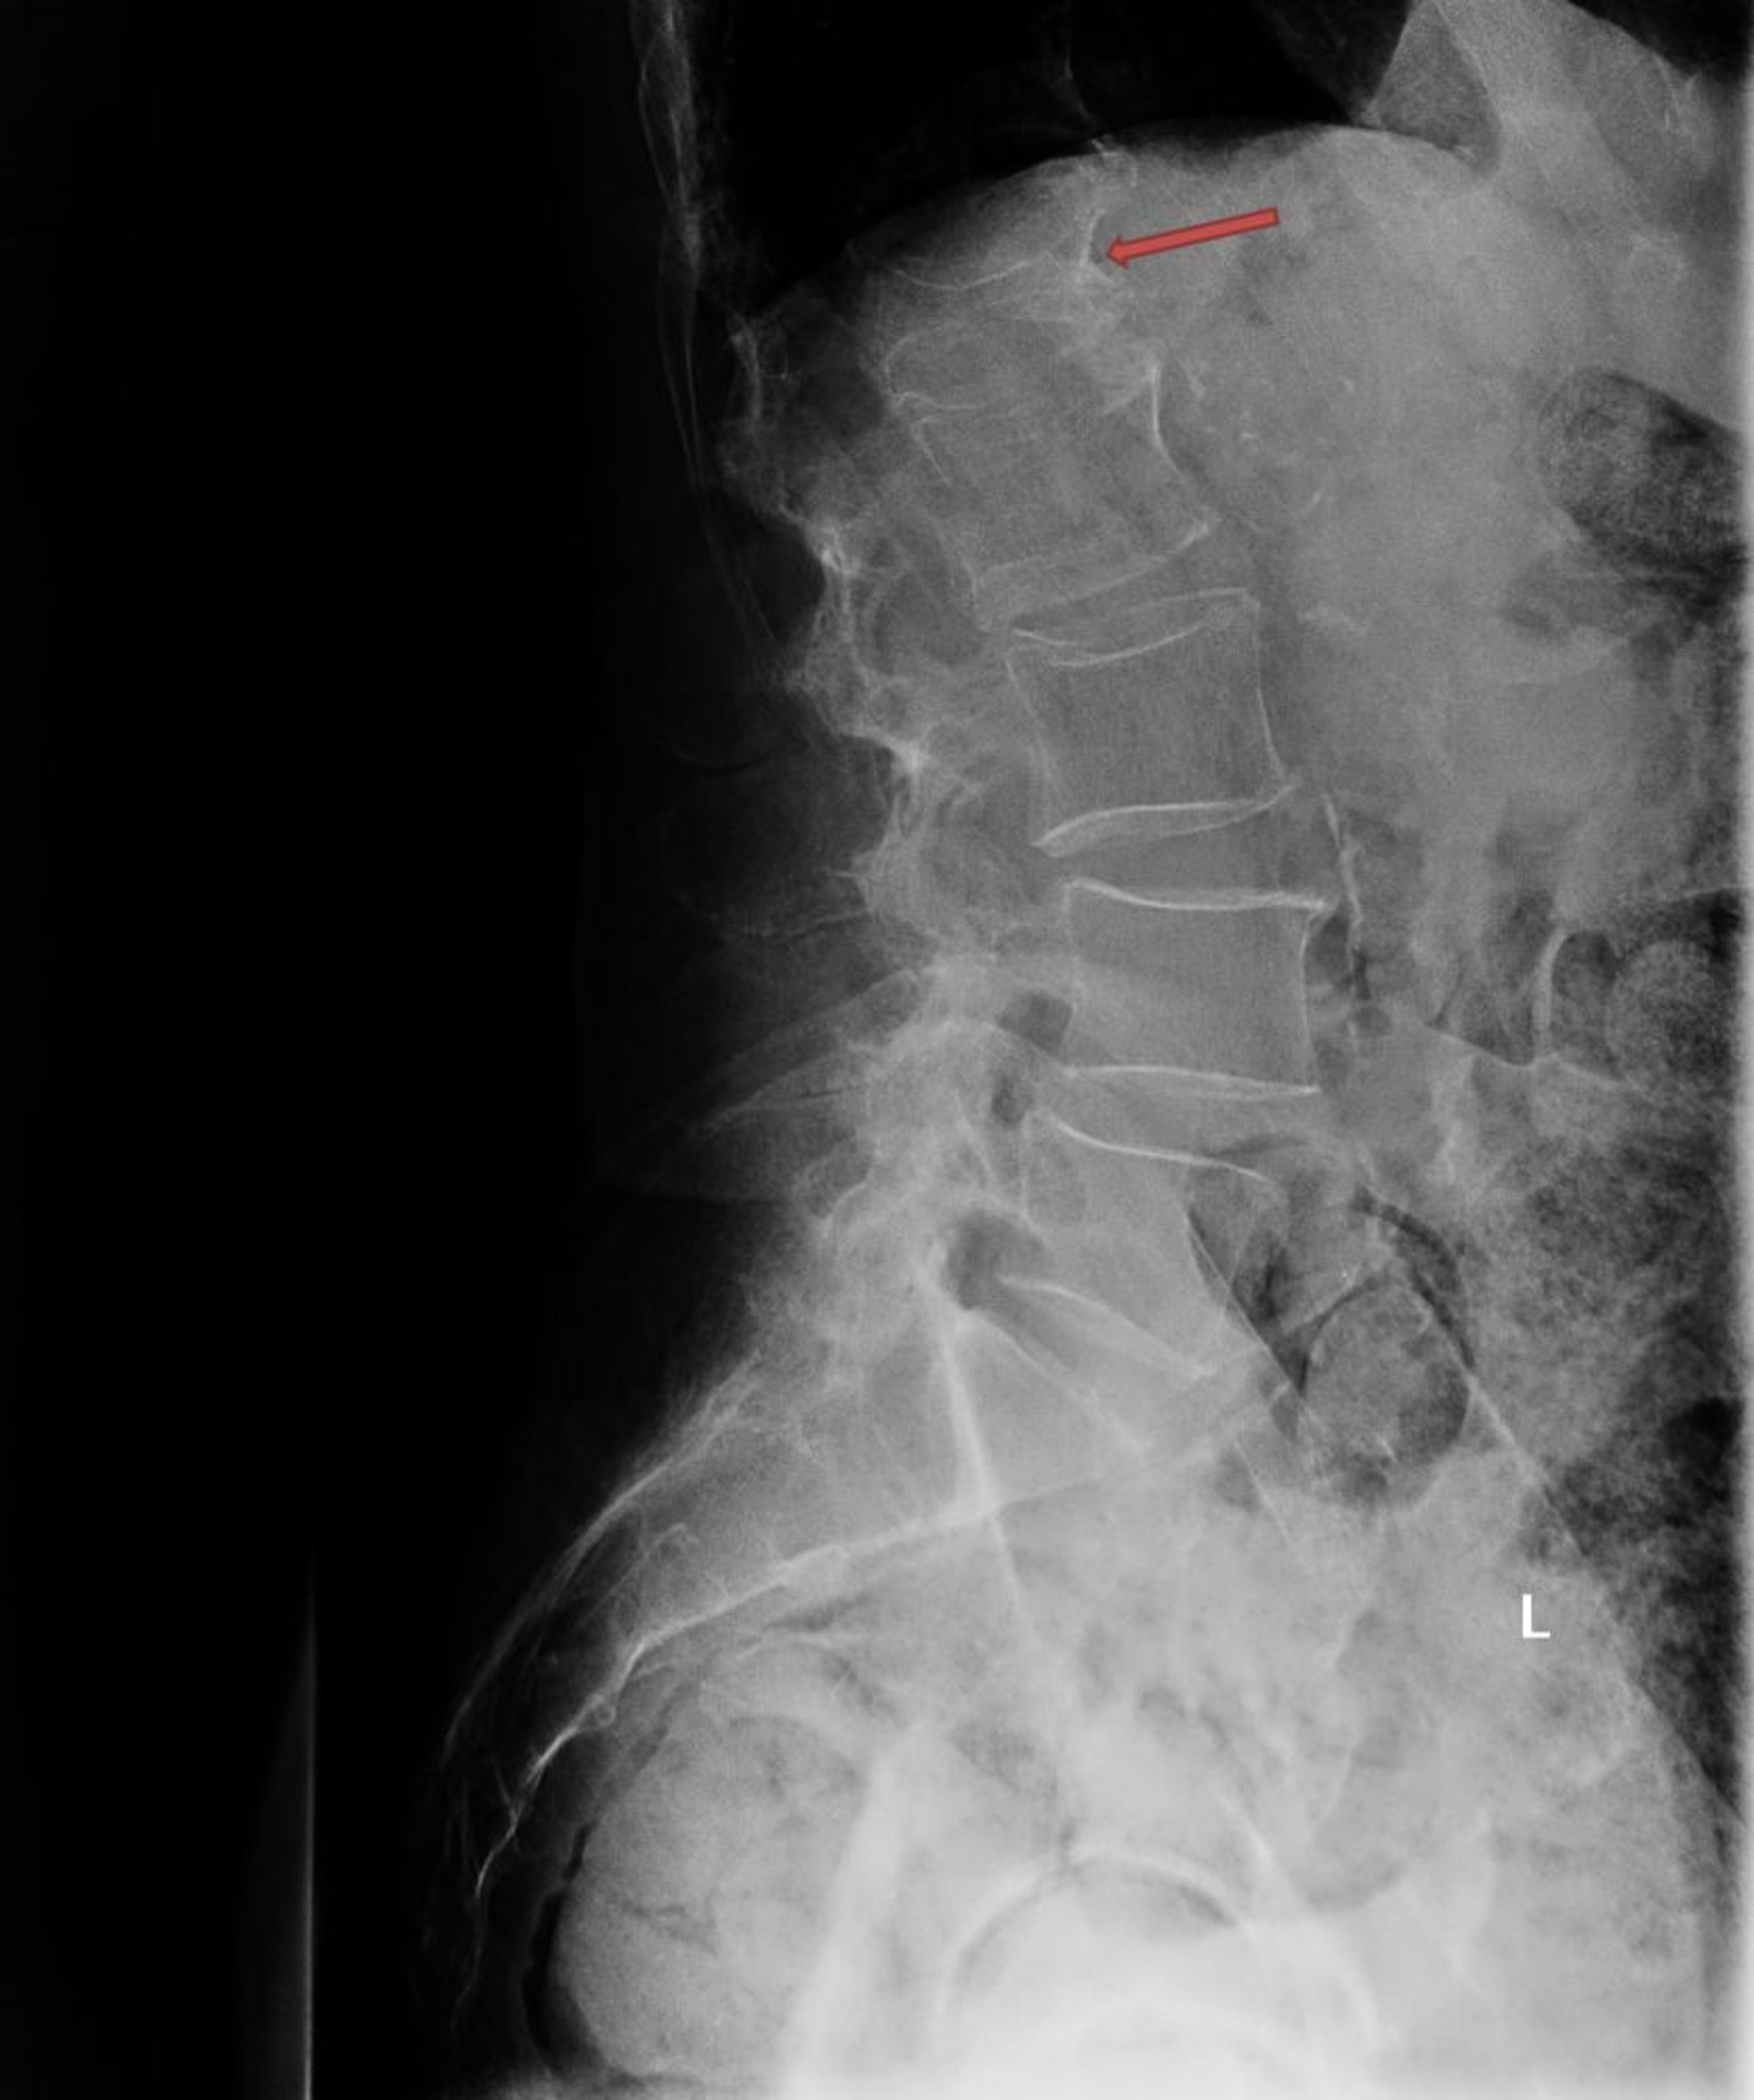

Fratura por compressão osteoporótica

Essa radiografia mostra fratura osteoporótica grave por compressão da primeira vértebra lombar (L1; seta).

Photo courtesy of Marcy B. Bolster, MD.